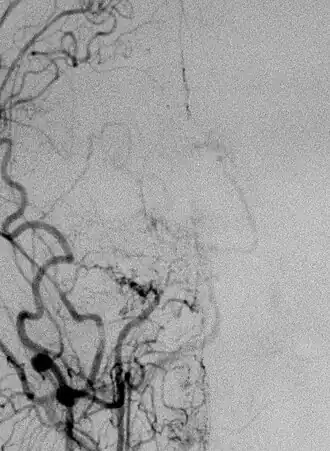

Боле́знь моямоя (от яп. もやもや — клуб дыма, туман) (БММ) — редкое хроническое прогрессирующее заболевание сосудов головного мозга, для которого характерно медленное (в течение месяцев и лет) сужение просвета внутричерепных сегментов внутренних сонных артерий (ВСА) и начальных отделов передних мозговых артерий и средних мозговых артерий вплоть до их окклюзии. Яркая отличительная черта заболевания — формирование сети коллатеральных сосудов на основании мозга, что на ангиограммах создает впечатление легкой дымки (G. Sébire и др., 2004)[2]. Именно этот признак в 1969 году дал современное название заболеванию: в переводе с японского «моямоя» обозначает «клуб дыма» (J. Suzuki и др., 1969)[3]. Первое описание БММ относится к 1957 году и принадлежит Takeuchi и Shimizu (K. Takeuchi и др., 1957) [4].

Диагностику заболевания строят исходя из клинической картины и дополнительных исследований. Наиболее информативны ангиография сосудов головного мозга, компьютерная томография, магнитно-резонансная томография, магнитно-резонансная ангиография, однофотонная эмиссионная компьютерная томография.

По Фукуи М. (1997)[8], радиологические критерии болезни следующие:

- наличие стеноза или окклюзии терминальных концов ВСА и проксимальных отделов передней и средней мозговых артерий;

- появление патологической сосудистой сети, видимой в области окклюзии;

- выявление при краниальной ангиографии признаков сосудистых изменений, типичных для БММ и носящих двусторонний характер.